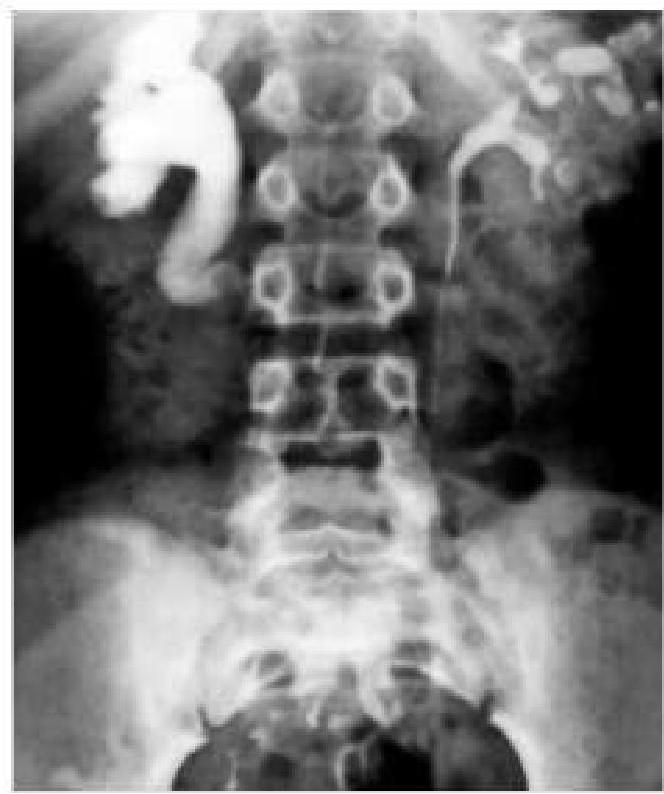

Question 1: A delayed intravenous urogram of a patient is given below. What is the likely diagnosis?

- A. Pelviureteric junction obstruction (Correct Answer)

Explanation: ***Pelviureteric junction obstruction*** - The image shows marked **dilatation of the renal pelvis and calyces** on the right side, with a relatively abrupt narrowing at the junction of the pelvis and ureter. - The delayed nature of the urogram suggests **impaired drainage** of contrast from the renal pelvis, accumulating proximal to the obstruction. *Putty kidney* - A "putty kidney" (or **autonecrotic kidney**) refers to a chronic, severely diseased kidney, often seen in end-stage **renal tuberculosis**, that has become calcified and non-functional. - This image demonstrates active contrast excretion and pelvicalyceal dilatation, not a calcified, non-functional organ. *Staghorn calculus* - A staghorn calculus is a **large, branched kidney stone** that occupies a significant portion of the renal collecting system. - While it can cause hydronephrosis, the image does not show a dense, radiopaque calculus filling the collecting system. *Cystic kidney* - **Cystic kidneys**, such as in polycystic kidney disease, are characterized by multiple fluid-filled sacs within the kidney parenchyma. - The image depicts dilatation of the collecting system, not diffuse cystic changes throughout the renal parenchyma.